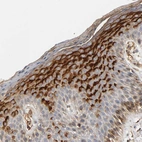

Immunohistochemical staining of human fallopian tube shows strong cytoplasmic granular positivity in glandular cells.